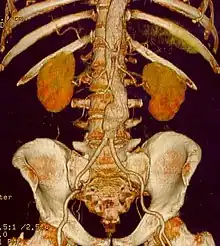

Abdominal aortic aneurysm

Abdominal aortic aneurysms (AAAs) are more common than their thoracic counterpart. One reason for this is that elastin, the principal load-bearing protein present in the wall of the aorta, is reduced in the abdominal aorta as compared to the thoracic aorta. Another is that the abdominal aorta does not possess vasa vasorum, the nutrient-supplying blood vessels within the wall of the aorta. Most AAA are true aneurysms that involve all three layers (tunica intima, tunica media and tunica adventitia). The prevalence of AAAs increases with age, with an average age of 65–70 at the time of diagnosis. AAAs have been attributed to atherosclerosis, though other factors are involved in their formation.[7]

The diagnosis of an abdominal aortic aneurysm can be confirmed by the use of ultrasound. Rupture may be indicated by the presence of free fluid in the abdomen. A contrast-enhanced abdominal CT scan is the best test to diagnose an AAA and guide treatment options.[10]